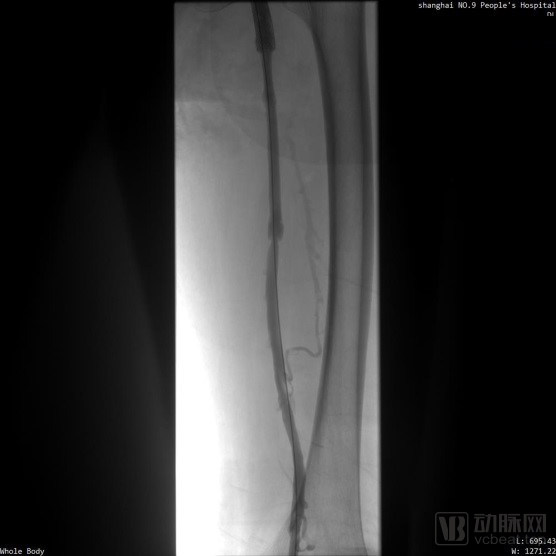

※ 取栓手术血栓清除情况: